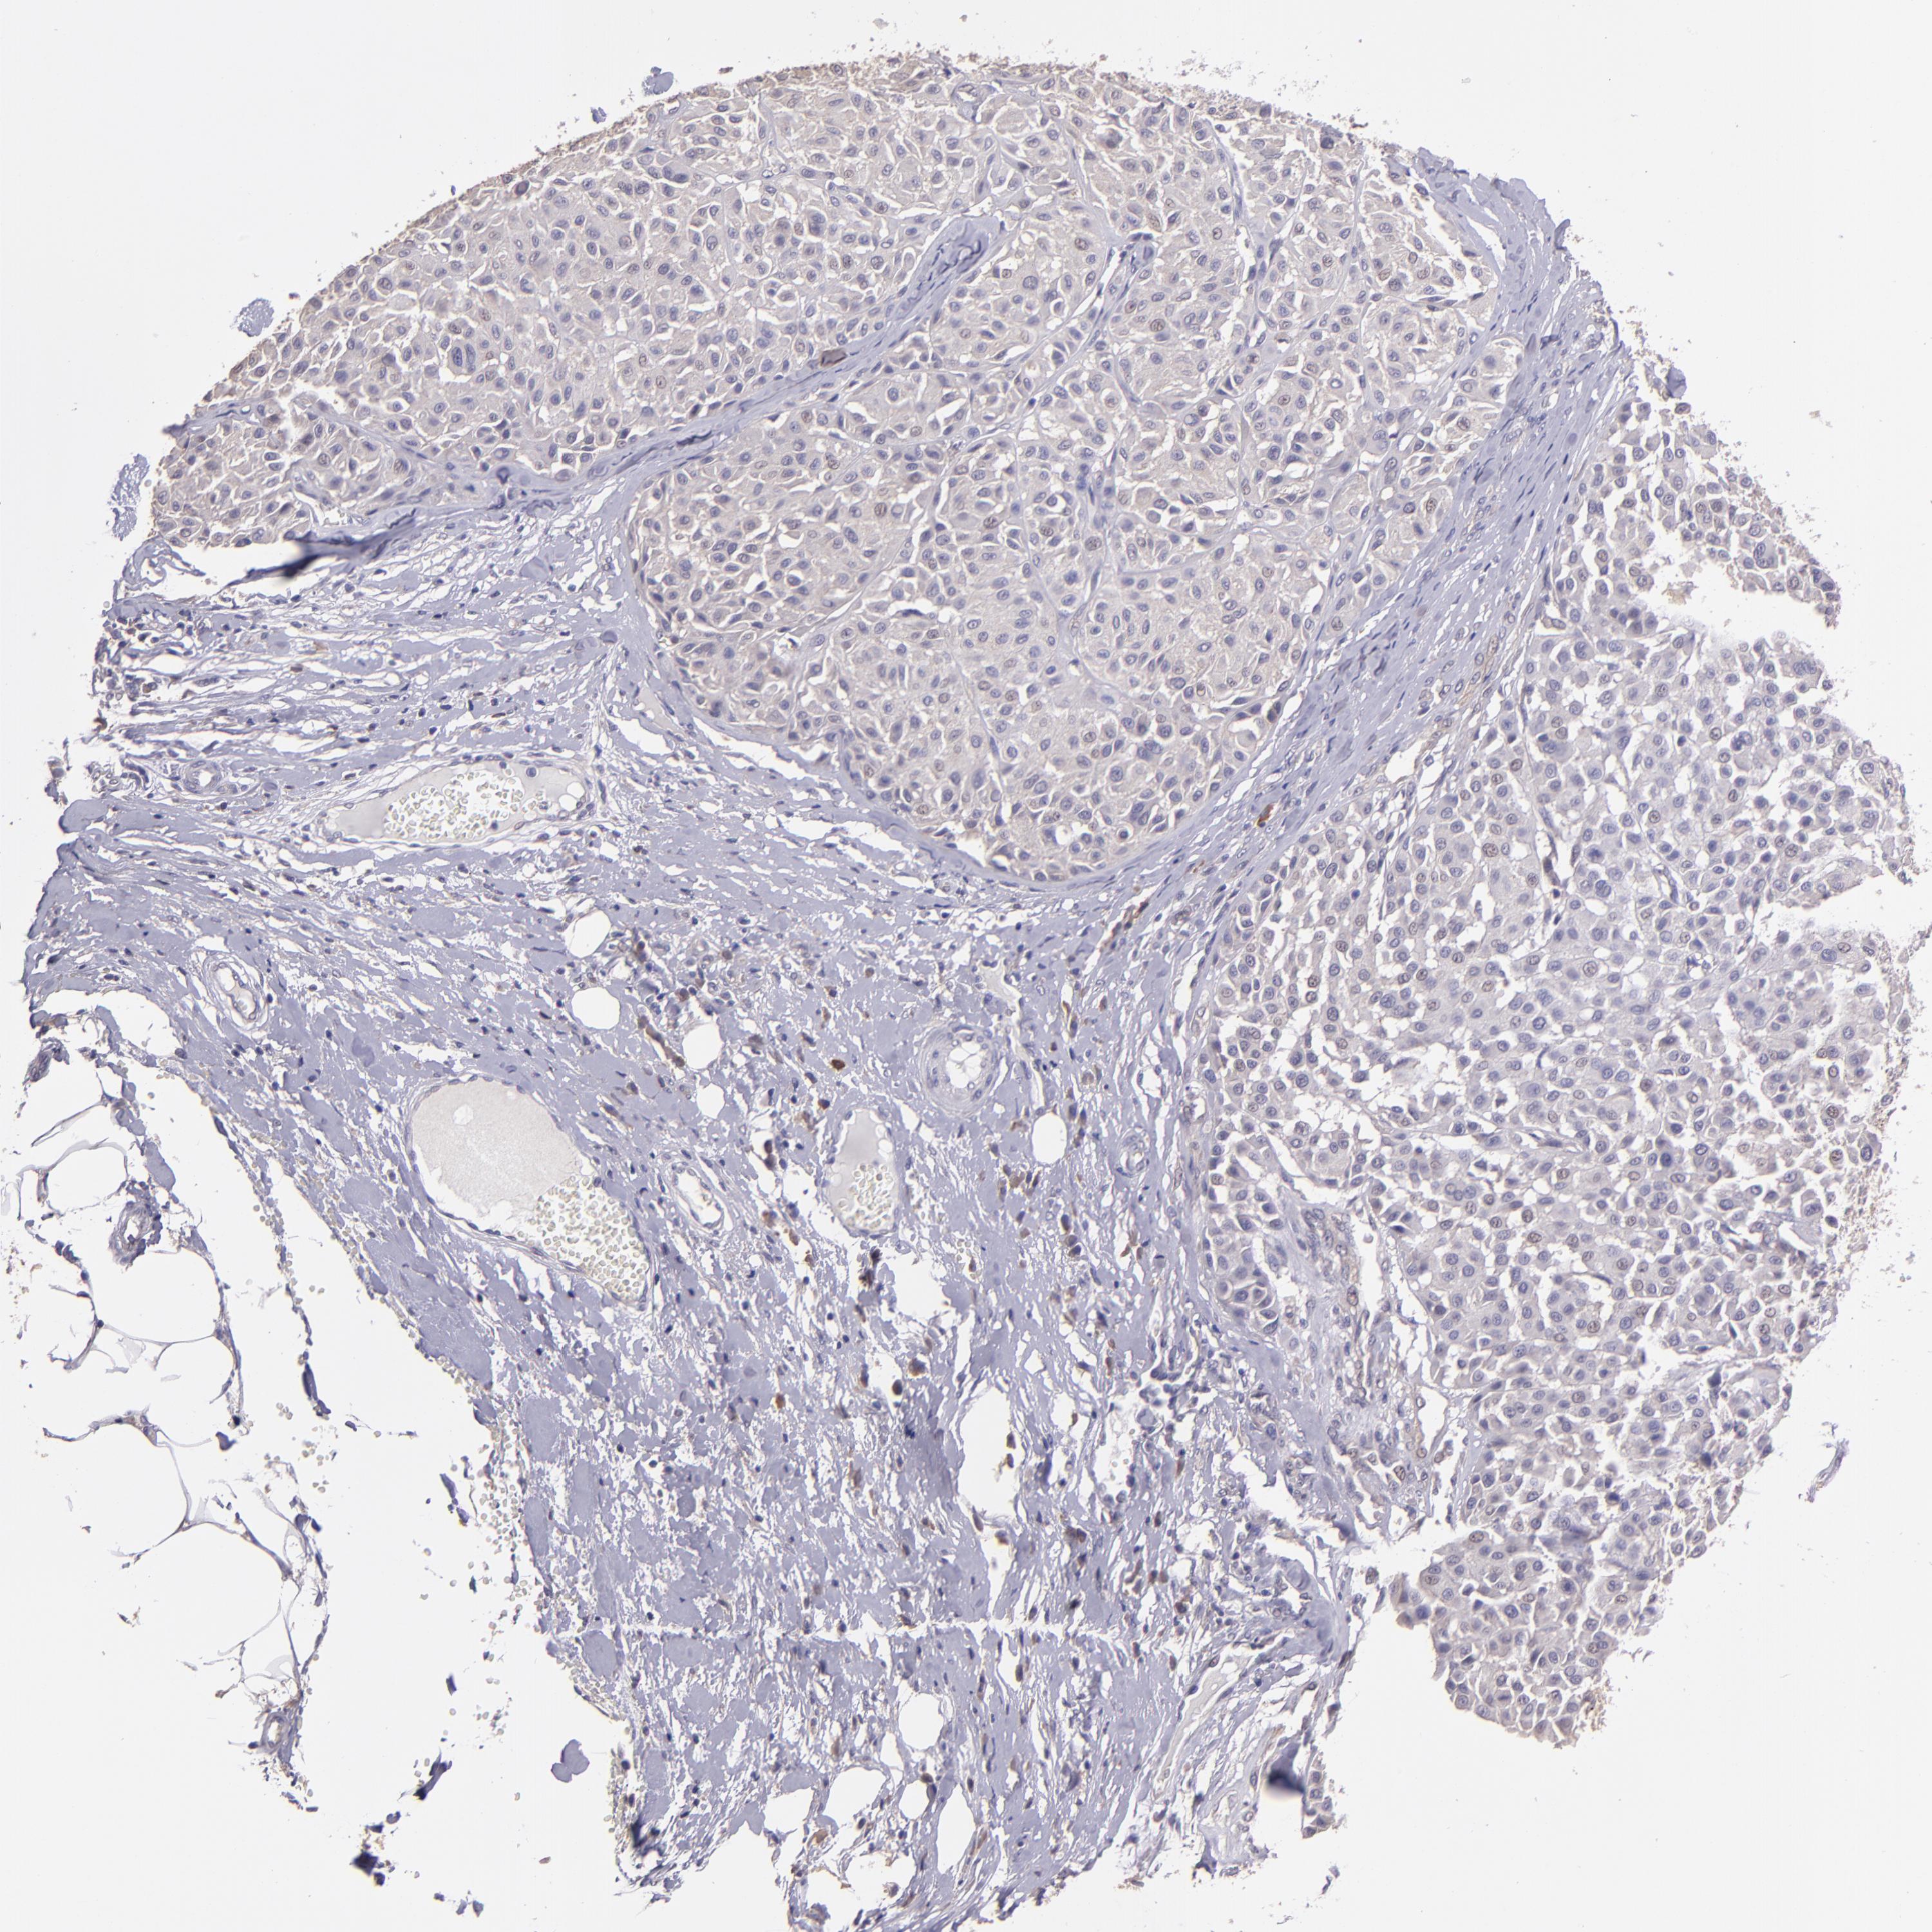

MELANOMA - Protein expressioni

A mouse-over function shows sample information and annotation data. Click on an image to view it in a full screen mode. Samples can be filtered based on level of antibody staining by selecting one or several of the following categories: high, medium, low and not detected. The assay and annotation is described here.

Note that samples used for immunohistochemistry by the Human Protein Atlas do not correspond to samples in the TCGA dataset.

Antibody stainingi

Antibody staining in the annotated cell types in the current human tissue is reported as not detected, low, medium, or high, based on conventional immunohistochemistry profiling in selected tissues. This score is based on the combination of the staining intensity and fraction of stained cells.

Each image is clickable and will lead to virtual microscopy that enables deeper exploration of all samples and also displays staining intensity scores, fraction scores and subcellular localization as well as patient and tissue information for each sample.

Antibody HPA001667

Antibody CAB016724

Staining

High

Medium

Low

Not detected

Intensity

Strong

Moderate

Weak

Negative

Quantity

>75%

75%-25%

<25%

None

Location

Nuclear

Cytoplasmic/membranous

Cytoplasmic/membranous,nuclear

Malignant melanoma, NOS

Malignant melanoma, Metastatic site